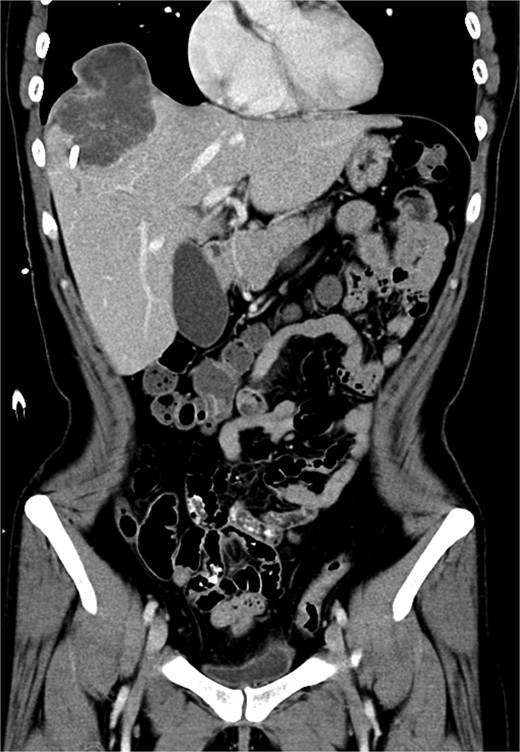

Upon admission to the GI ward, a repeat abdominal CT scan suggested a possible liver abscess. Drainage was performed on September, 2024, and empirical antibiotic therapy with ceftriaxone and metronidazole was initiated. Despite initial drainage and antibiotics, the patient continued to experience intermittent fever. A subsequent CT scan revealed a heterogeneous lesion measuring ~7.5 × 8.5 cm at S8 (Figs 2 and 3). A sono-guided liver biopsy was performed, and the pathological report indicated hepatic sarcomatoid carcinoma with variable positivity for CK and CK7, and negativity for CK20, glypican-3, ERG, and CD34 stains, suggesting a possible cholangiocarcinoma component. A general surgery (GS) consultation was obtained for suspected liver tumor management.